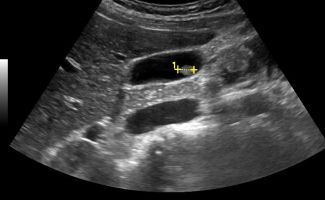

- Κυστικές αλλοιώσεις (κύστεις σε ήπαρ, νεφρούς, πάγκρεας)

- Συμπαγείς βλάβες όπως αιμαγγειώματα, αιμαγγειωμυολιπώματα, ή νεοπλάσματα στο ήπαρ, τους νεφρούς, και το πάγκρεας

- Σε περίπτωση νεφρολιθίασης: βαθμός διάτασης του πυελοκαλυκικού (αποχετευτικού) συστήματος του νεφρού, διερεύνηση της εντόπισης του λίθου (στο νεφρό, τον ουρητήρα ή την ουροδόχο κύστη)